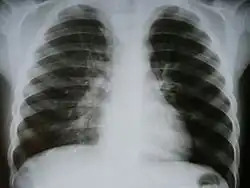

Инфильтрация при туберкулезе (справа)

Инфильтра́т (от лат. in — в; filtratus — процеженный) — скопление в тканях организма клеточных элементов с примесью крови и лимфы. Наиболее часто встречаются воспалительный и опухолевый инфильтрат. Воспалительный инфильтрат состоит преимущественно из полиморфноядерных лейкоцитов (гнойный инфильтрат), эритроцитов (геморрагический инфильтрат), лимфоидных клеток (круглоклеточный инфильтрат), гистиоцитов и плазматических клеток (гистиоцитарно-плазмоклеточный инфильтрат) и других. Такие инфильтраты могут рассасываться, расплавляться, подвергаться склерозированию, с образованием каверны, абсцесса, рубца и тому подобного. Опухолевый инфильтрат состоит из опухолевых клеток различной природы (карцинома, саркома) и является проявлением инфильтрирующего роста опухоли. С образованием инфильтрата ткань увеличивается в объёме, меняет цвет, становится плотнее, иногда болезненна. В хирургической практике инфильтратом называется уплотнение, возникающее в тканях при их пропитывании анестезирующим (обезболивающим) раствором (смотри Местная новокаиновая блокада).